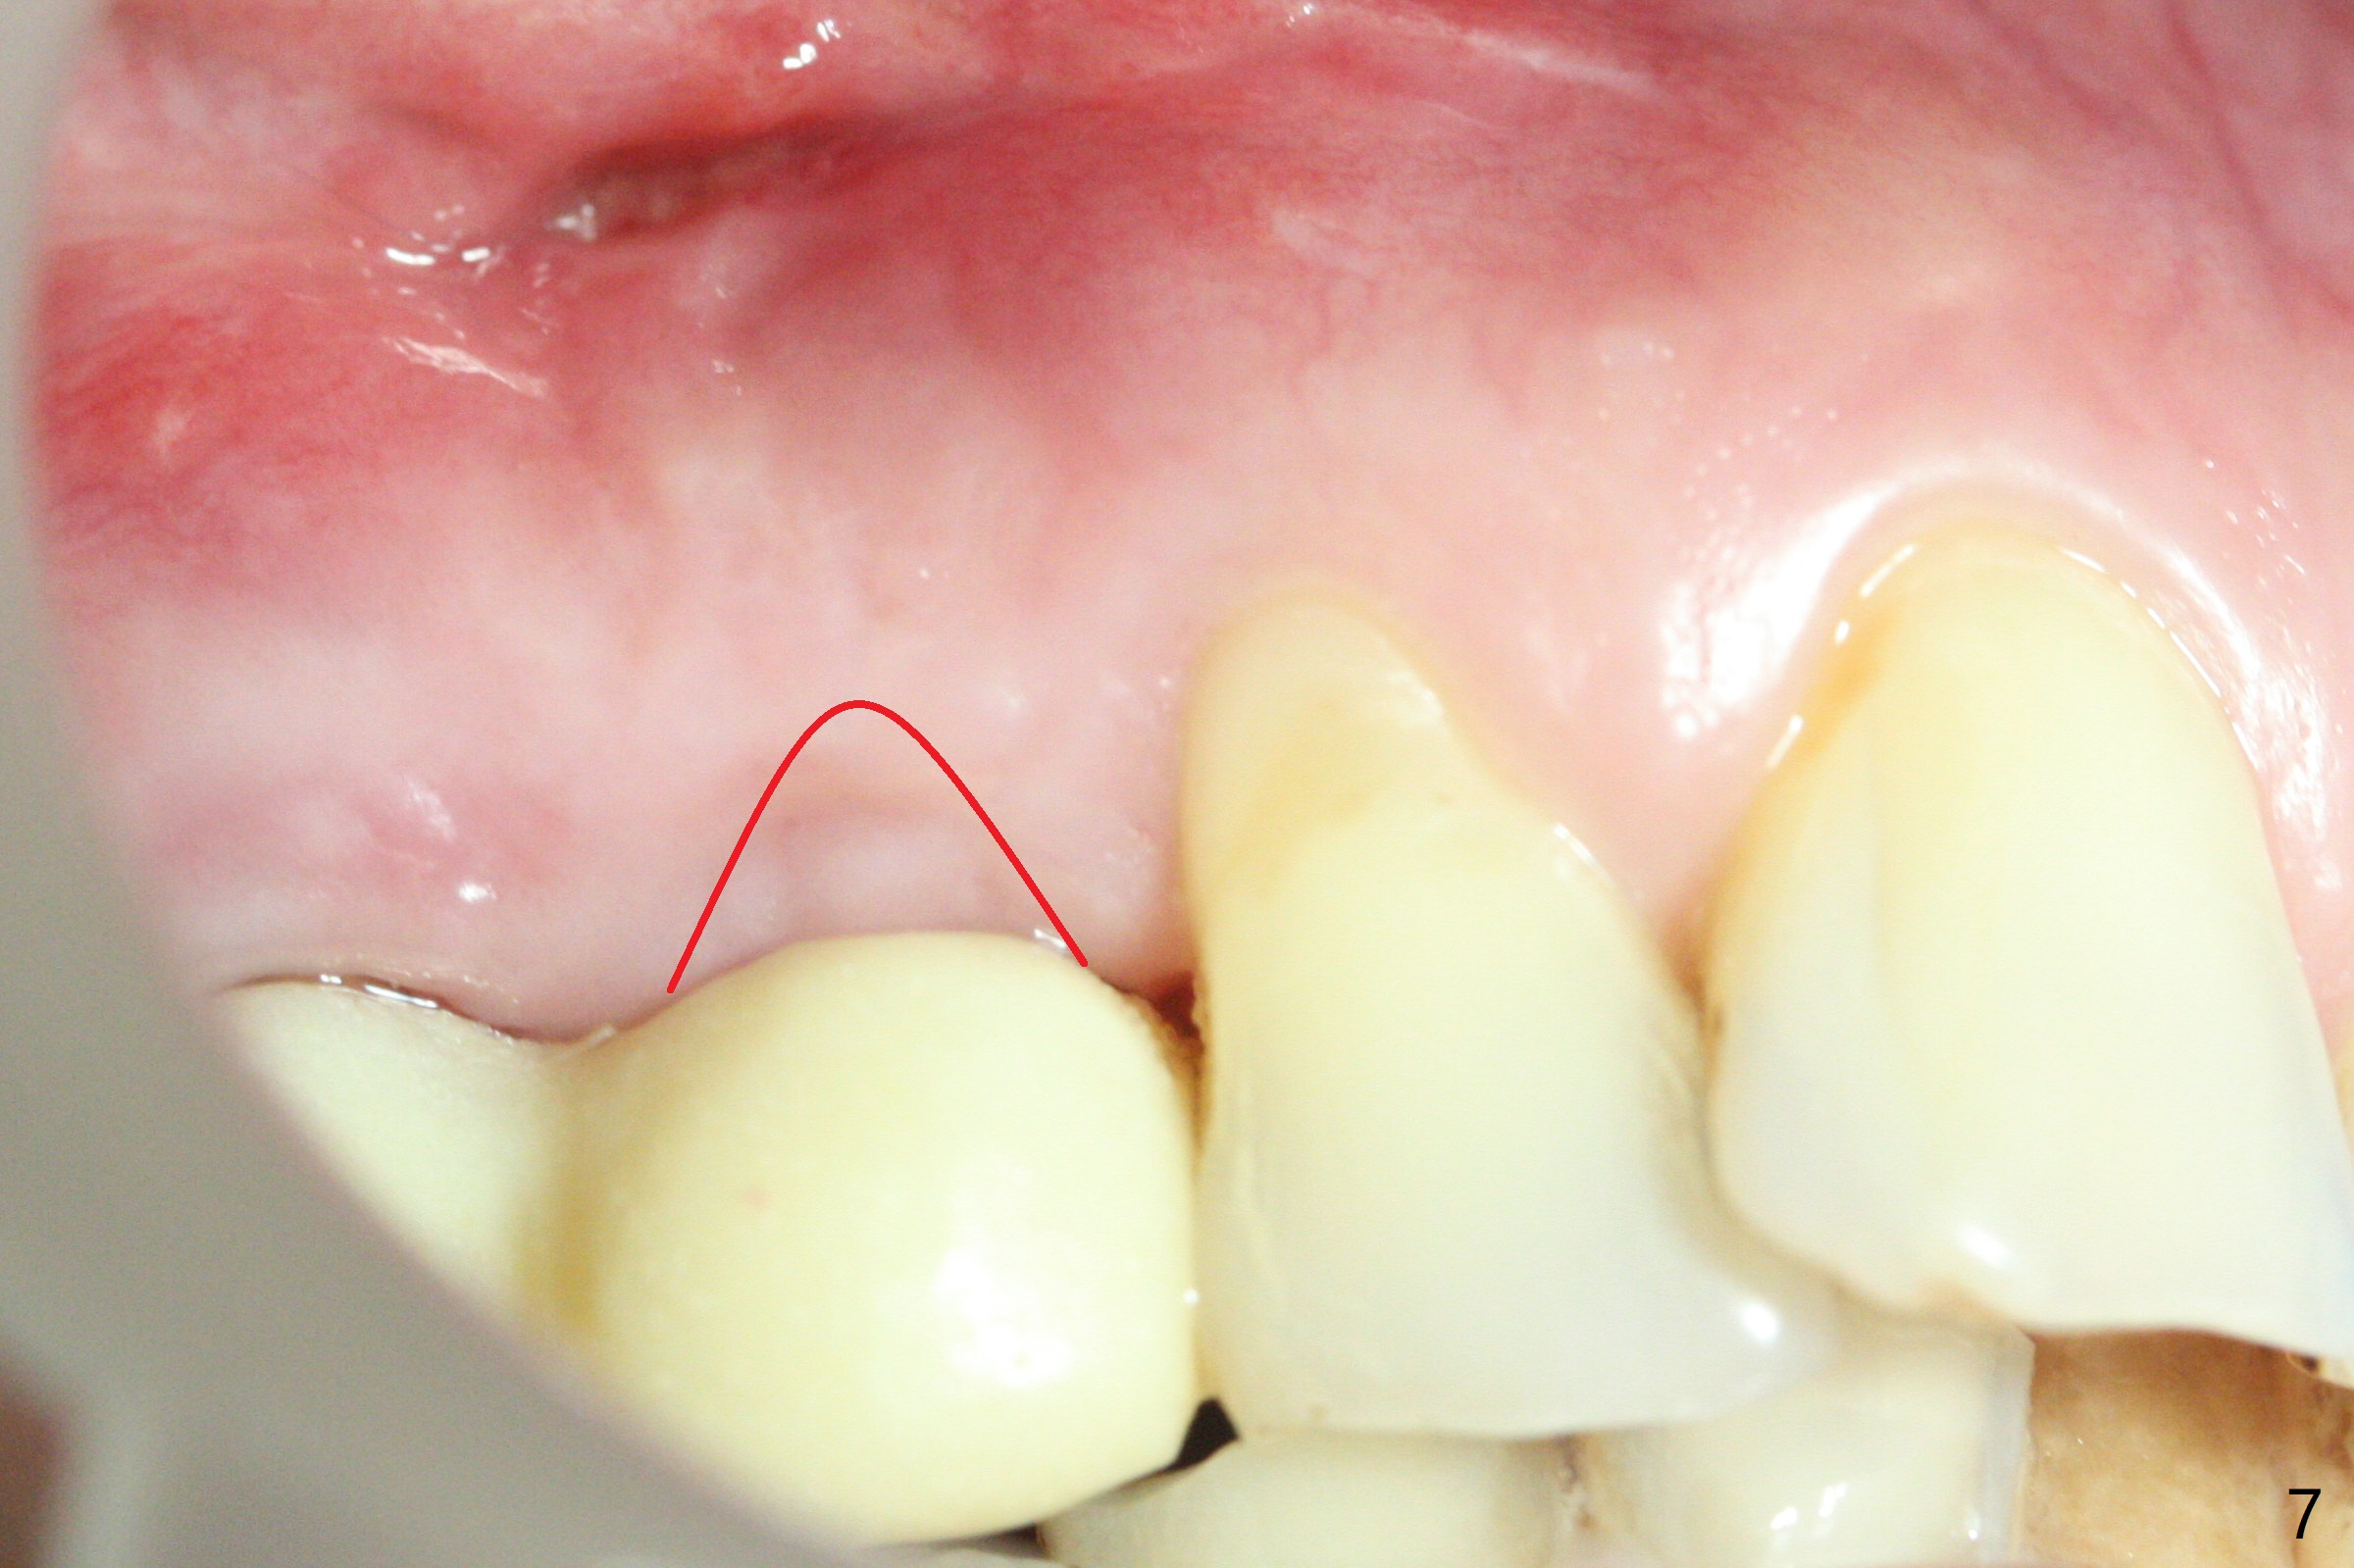

Osteotomy starts with guide and 2.2 mm drill for initial 3.5 mm palatal. A semilunar incision is made buccal to remove the impacted canine (#6 by sectioning). With direct vision buccal and palatal, the final osteotomy is finished free hand with 1.2 and 1.5 mm drills. Initially buccal perforation occurs, the osteotomy route is corrected later (Fig.1). When a 2.5x15 mm 1-piece implant is being placed, it perforates into the buccal concavity again. After redirection, the trajectory seems to be acceptable (Fig.2: CT coronal section). Three coronal implant threads are exposed partially palatal (Fig.3: CT 3-D palatal view). The implant is then turned 2-3 times with insertion torque reaching 40 Ncm. The incision is closed with suture following Osteogen plug placed in the most coronal portion of the socket (Fig.4 P) and allograft (*) in the remaining socket around the apical portion of the implant as well as palatal. The incision does not heal 1 month postop (Fig.5). PRF membrane will be placed next visit. Next visit the wound in fact is healing (Fig.6). PRF is unnecessary. The patient will return for impression 3 months postop. To be cosmetically pleasing, prepare local anesthetic and Laser for gingivectomy (Fig.7 red curved line). There is no bone loss around the implant 3.5 months postop (Fig.8). With topical, minor gingivectomy with laser creates papillae mesial and distal to the implant (Fig.9, 10 (incisal view)). After reline, there is appearance of a canine (Fig.11). The patient returns for impression 5 months postop; there is bone around the apex of the implant (Fig.12 *). The hard and soft tissues remain healthy when final restoration is delivered (Fig.13,14). The buccal plate reforms and #6 socket heals 12 months postop (6 months post cementation, Fig.15). The gingiva remains healthy at #4-6 nearly 2 years post cementation (Fig.16).